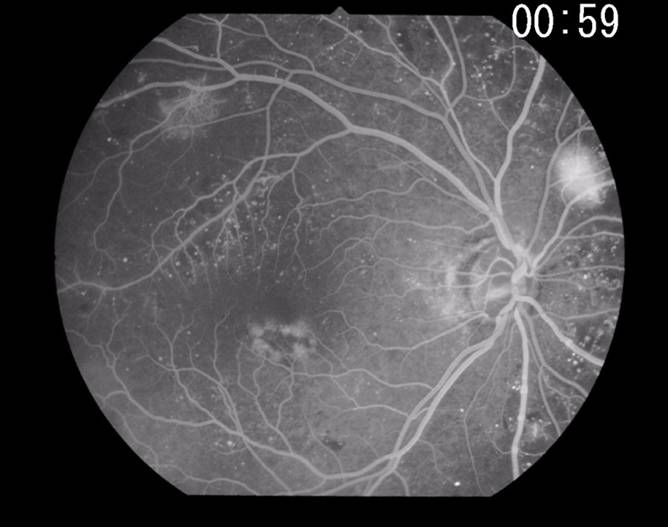

視力検査、眼圧検査、眼底検査を行い、網膜症の程度を判断するために蛍光造影眼底検査(FAG)を行います。また、視力低下の原因となる黄斑症に対してはFAG検査、OCT検査を行います。

左上:蛍光造影眼底検査写真

造影剤を血管に注入して病変部からの造影剤の漏れ、血液無灌流域の状態をみます